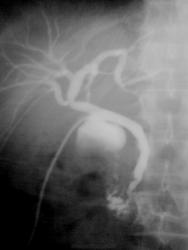

Случай 1.

Послеоперационная чрездренажная холангиография. У хирурга был влпрос по снимку, какой, по вашему?)))

1. Надежда в вопросе хирурга: а может это, совершенно случайно, не несостоятельность анастомоза, а в 12-перстной? Контуры верхние ровные, странно... Может, чего-то недопоняла.

1. Хирург наоборот, луковицу 12 п кишки принял за затек...потом успокоился и заулыбался)))

Вот и говорю, странный какой затёк, но луковка какова - красава! laugh

На первом снимке контрастировано ложе желчного и, вероятно вследствие антиперистальтики, конраст по 12перстной вверх к желудку пошел.

По первому случаю: Я тоже принял лдпк(???) за затек. Что за операция такая, где ЛДПК подводят к шейке бывшего пузыря? Снимки сделаны с разницей  в 1-2 секунды? Потому как если это ЛДПК, то были бы видны Керкринговы складки в последующем.

Нет, коллега, это не ложе желчного, это ЛУКОВИЦА 12 п кишки, а в желудке контраста нет.

Суммация теней и всех делов...ЛДПК никуда не подводят. Снимок один - в положении лежа на спие (сейчас у меня, увы, нет цифровой скопии....), гляньте по ссылке там есть еще несколько схожих случаев. А нисходящее колено просто сократилось в этот момент...

Случай №1. Тень луковицы принял бы за затёк. Только смущало слева наличие контраста. Вероятно и дуоденальногастральный рефлюкс имеется?